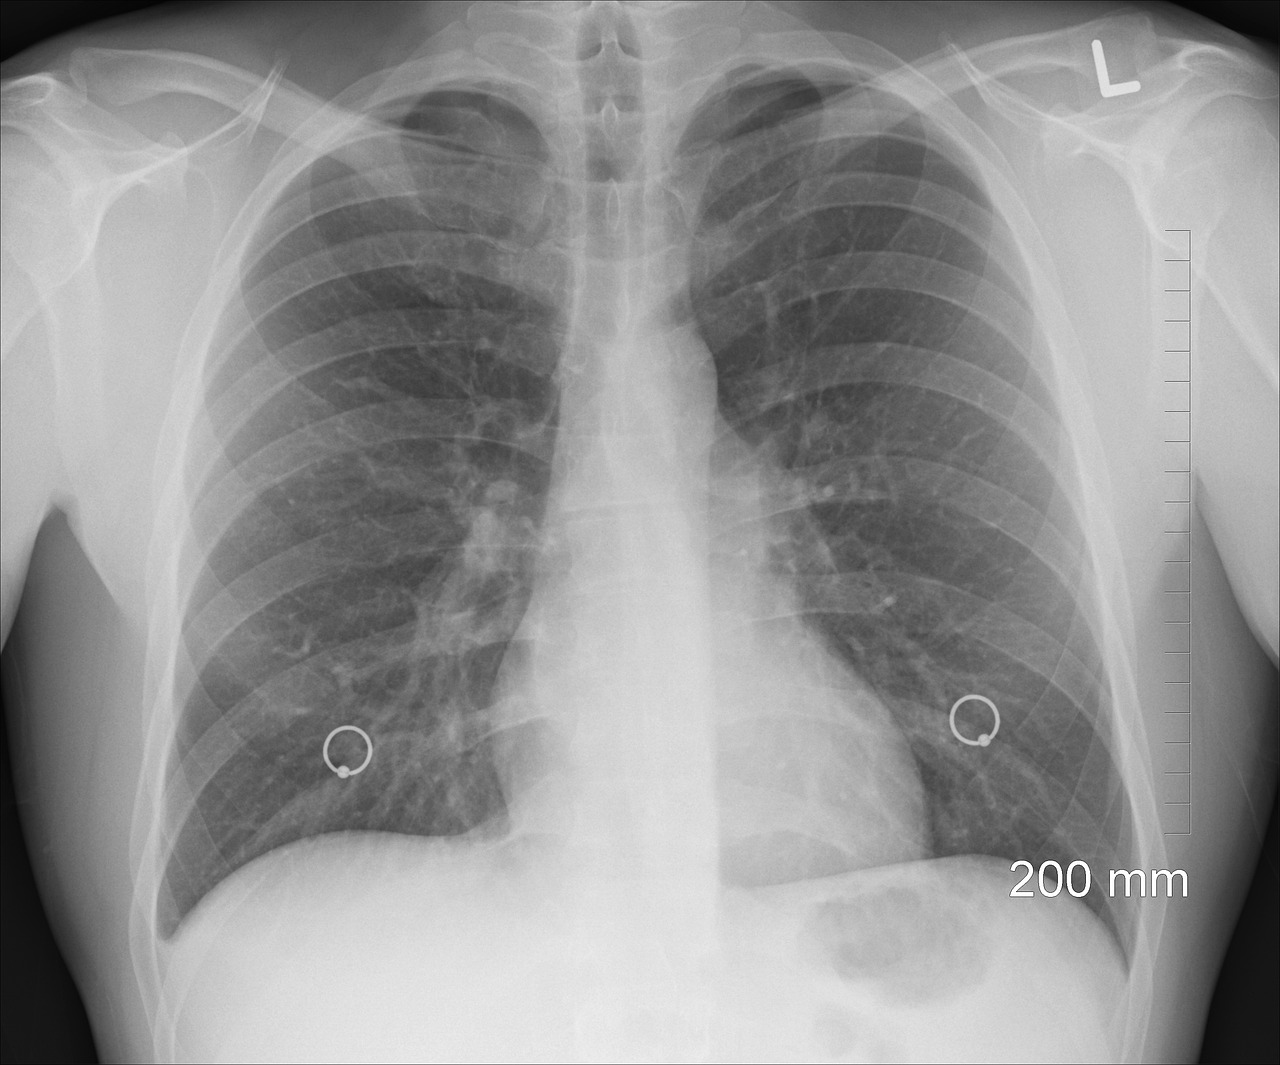

La detección temprana del cáncer, de cualquier tipo, es clave para acceder a un tratamiento a tiempo. Por ejemplo, si eres un fumador de mucho tiempo o estuviste cerca de uno, puedes hacerte una prueba de detección.